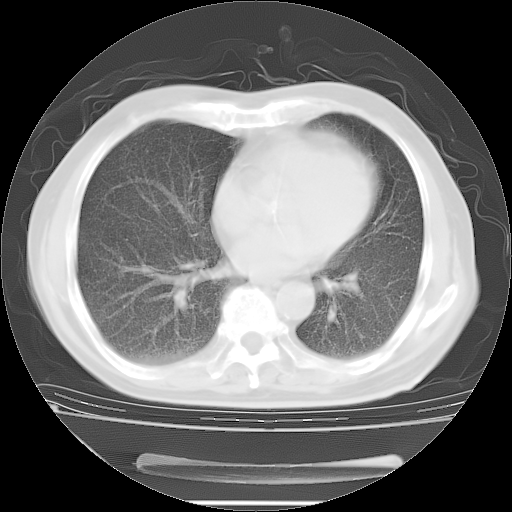

今天复查肺部CT,发现双肺广泛磨玻璃样改变。所以我把3月19日和5月9日相隔50天的肺部CT上传。请大家会诊。

2009年3月19日肺部CT片。

2009年3月19日肺部CT

5月9日肺部CT(在4月27日齐鲁医院肺部CT描述部分肺组织磨玻璃样改变,12天后肺组织广泛磨玻璃样改变)